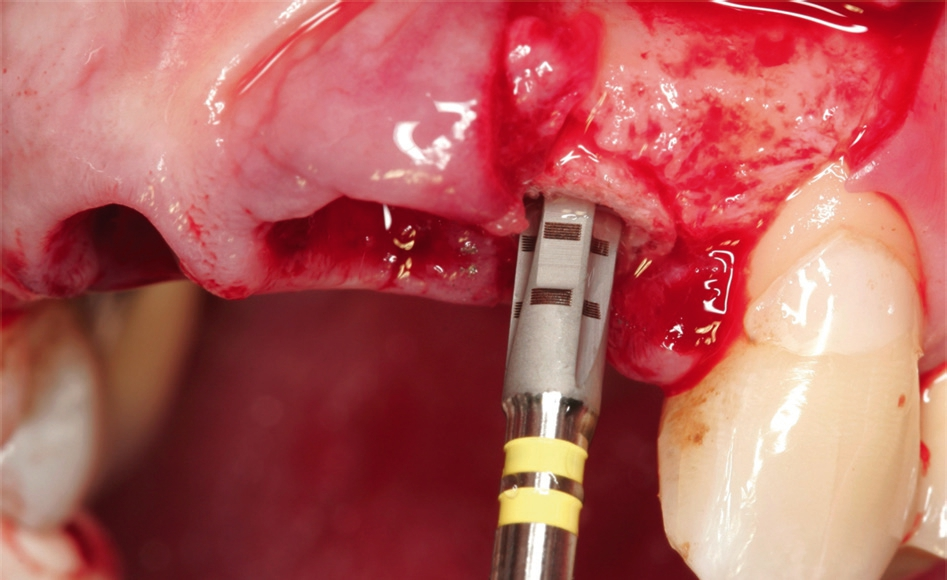

Nach Extraktion der Zähne 12, 22, 11, 21 wurde mit dem Behandlungsprotokoll für maxgraft® bonering begonnen. Nach Pilotbohrung zur Festlegung der Implantatposition wurde mit einem 6 mm Trepan die Augmentationsstelle des maxgraft® bonerings vorbereitet (Abb. 5). Danach folgte das Planieren des Ringbettes mit einem 6 mm Planator, um ein flaches Ringbett zu generieren (Abb. 6).